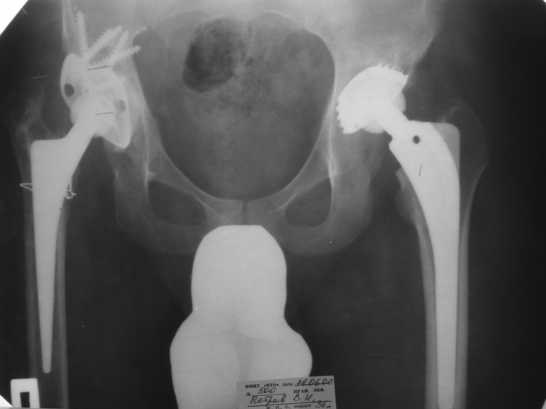

1999г. ревизионное протезирование правого ТБС и вновь инфекционная нестабильность - протез удален. 2000 г. установлено кольцо Мюллера и ножка типа Споторно справа (рис. 1).

2003 г. нестабильность тазового компонента (рис. 2) - протез удален.

Обращение в нашу клинику в 2008 г. - демонтаж аппарата (рис. 4). Сегодня укорочение 8 см. Слева - протез стабилен, безболезнен.